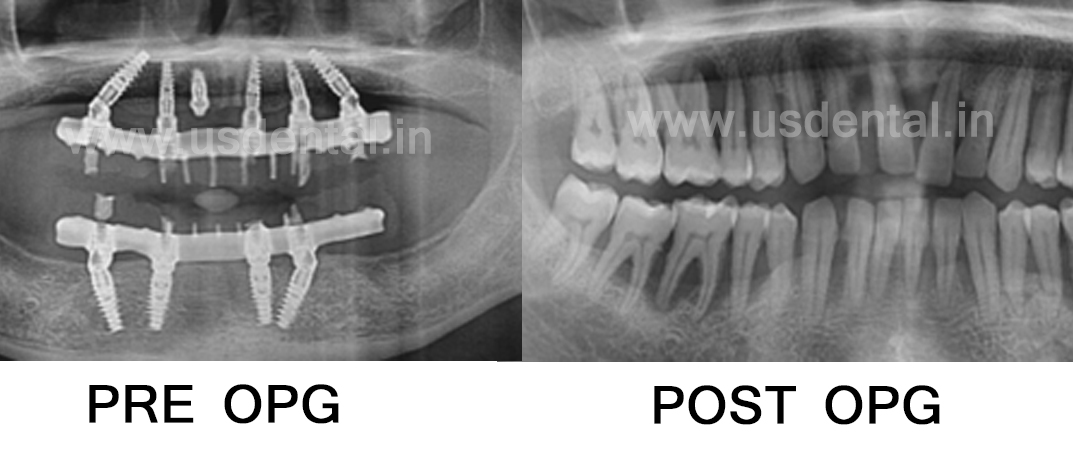

A 30-year-old patient from the USA visited us in 2015 with the chief complaint of mobility teeth and difficulty in eat. The patient wanted to replace his teeth, as he was unable to eat properly. On examination, the patient was diagnosed with aggressive periodontitis. All teeth were mobile, with noticeable gum recession. Significant bone loss was also observed on the CBCT scan. Possible treatment options, including removable complete dentures, implant-supported over dentures, and implant-supported fixed dentures, along with their respective advantages and disadvantages, were explained to the patient. The patient opted for fixed teeth and decided to proceed with implant surgery. Teeth from both the upper and lower arches were extracted, and implants were placed. After a healing period of three months, hybrid dentures for both the upper and lower arches were delivered. The patient returned to our clinic after a decade with a complaint of fractured front teeth in his denture. A detailed clinical examination along with X-ray imaging confirmed that all previously placed implants were intact, with no signs of bone loss or complications. A new set of hybrid dentures for both the upper and lower jaws was carefully designed and delivered, restoring both aesthetics and function.